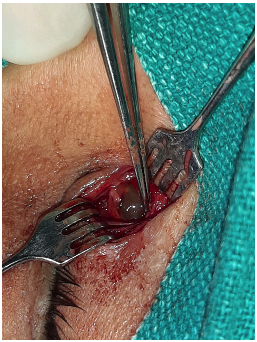

Examination of the eye was essentially normal, and best corrected visual acuity was 6/6 in both eyes. Lacrimal syringing revealed patent lacrimal pathway on both sides. Nasal examination ruled out any local pathology. Noncontrast computed tomography orbit axial scan showed nodular soft tissue in the middle part of the right nasolacrimal duct (Figure 2). An excision biopsy was planned. A cystic mass measuring 0.5 × 0.5 × 0.3 cm (Figure 3) was excised in toto; the lesion appeared to be separate from the nasolacrimal duct, and probing confirmed the same.

On gross examination, the excised specimen consisted of a greyish brown tissue measuring approximately 0.5 × 0.5 × 0.3 cm3 with a soft consistency (Figure 3). Microscopically, the lesion consisted of a cyst wall lined by a double-layered epithelium and surrounded by fibrous tissue. The outer layer was lined by flat to cuboidal cells and by an inner layer of columnar cells with eosinophilic cytoplasm and many cells with vacuolated cytoplasm. Stratification was seen at a few places, and the findings were suggestive of benign nasolacrimal duct cyst consistent with apocrine hidrocystoma (Figure 4).